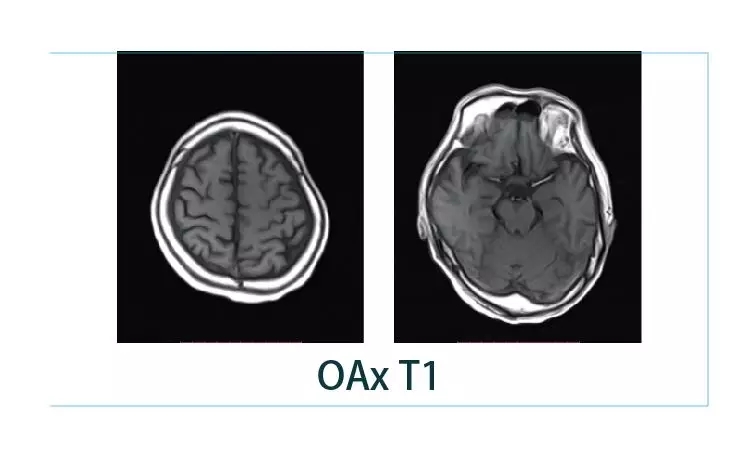

【朗润影像档案】20190125磁共振影像病例结果讨论

1548727074790396.jpg1548727094576003.jpg1548727106975217.jpg1548727127776211.jpg